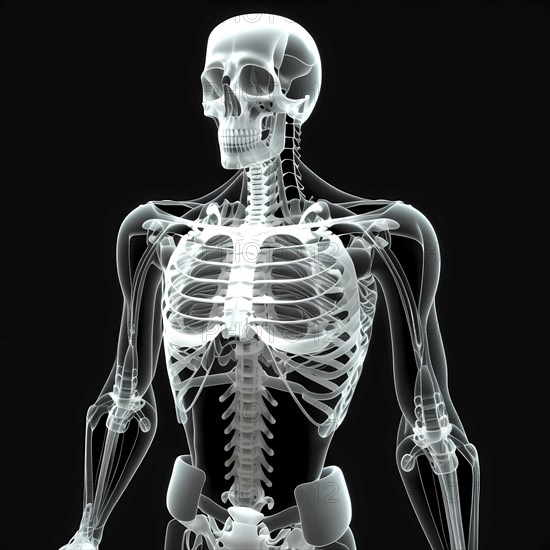

Sujet

Légende

**Image générée par intelligence artificielle**

Medical X-ray illustration, Translucent human body with skeleton, AI generated

Image générée par intelligence artificielle